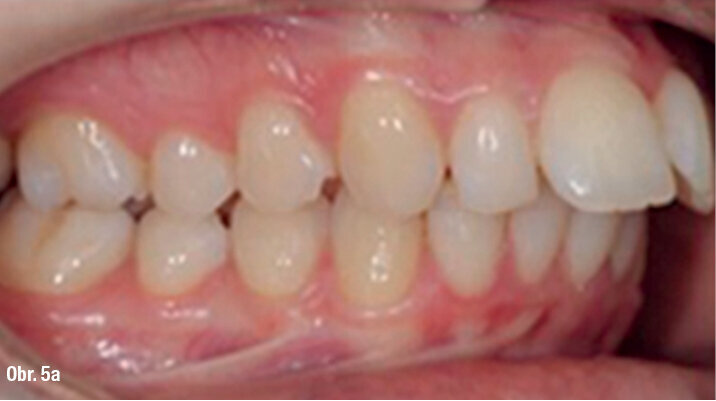

25letá pacientka požadovala estetickou ortodontickou léčbu, kterou nebylo jednoduché naplánovat vzhledem k tomu, že je umělkyní a cestuje po celé Evropě. Během vyšetření byla diagnostikována II. třída 1. oddělení, mírné stěsnání v dolní čelisti a středně těžké stěsnání v čelisti horní. Incizální schůdek byl 10 mm. Profilová zkouška jasně ukazuje protruzní postavení rtů (obr. 1a–c). Pacientka odmítla extrakční nebo ortodonticko-chirurgickou léčbu. Vhledem k jejím požadavkům na estetiku byl léčebný plán stanoven takto: léčba fóliovými aparáty Invisalign (Align Technology) s výsledným postavením molárů i špičáků v I. třídě, které bude dosaženo postupnou distalizací horních molárů s pomocí kompozitních attachmentů na všech distalizovaných zubech a tahů II. třídy (obr. 2, 3). Pacientce bylo doporučeno nosit fólie a tahy II. třídy nejméně 21 hodin denně. Dále pacientka používala přístroj AcceleDent 20 minut denně po celou dobu trvání ortodontické léčby. Fólie byly měněny každé 2 týdny, dokud nebyly druhé horní moláry plně distalizovány, potom každých 10 dnů, dokud nebyly první moláry ve své finální pozici, a nakonec každých sedm dní až do konce léčby.

ClinCheck (Align Technology) software navrhl k získání požadovaných výsledků 63 alignerů s předepsaným množstvím atachmentů a nasazením tahů II. třídy. Odhadovaná doba léčby byla přibližně 30 měsíců. Nicméně protože se pacientka rozhodla používat přístroj AcceleDent, léčba byla ukončena již po 18 měsících bez nutnosti refinementu, tedy s původně plánovanými 63 alignery (obr. 4a–c, 5a–c).

Klinický výsledek byl vynikající, postavení molárů i špičáků v I. třídě, vyhovující překus a předkus. I profil dolní třetiny obličeje byl výrazně lepší.